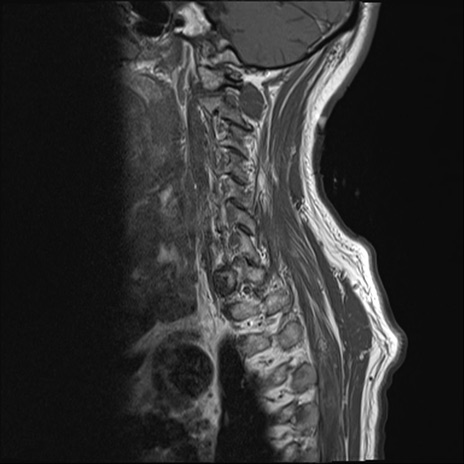

【整形】TIPS症例7 頚椎MRI T1WI(矢状断像)

頚椎MRI

T2WI(矢状断像)